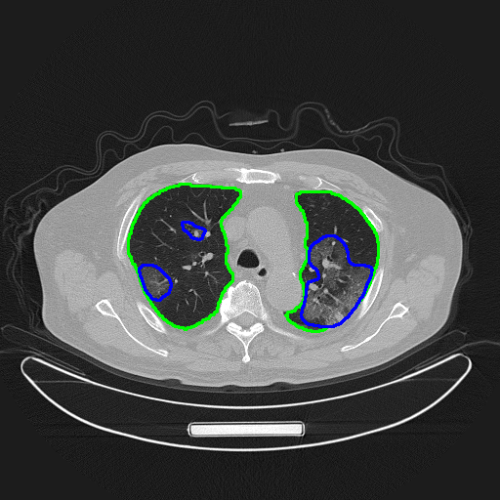

AI对病人肺部和新冠肺炎病灶做了精确的自动分割

“腾讯觅影”对新冠肺炎影像识别模型也做了针对性的优化。通过肺炎病灶区域的精确分割,提供定量分析,以方便影像医生在短时间内对患者病情的严重程度及发展过程做出准确评判。下一步还将提供病例随访等功能,方便医生快速比对患者病情,评估治疗效果。